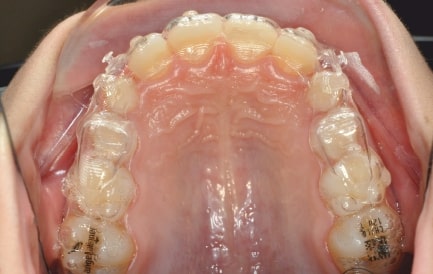

Initial Photos and datas

Clinical examination and diagnosis

DENTAL:

- Reduced Transversal Diameters

- Upper Archform enlargement (dental expansion)

- Normalize Overjet/Overbite (Lower Posterior Extrusion)

- Alignment/Leveling Both Arches